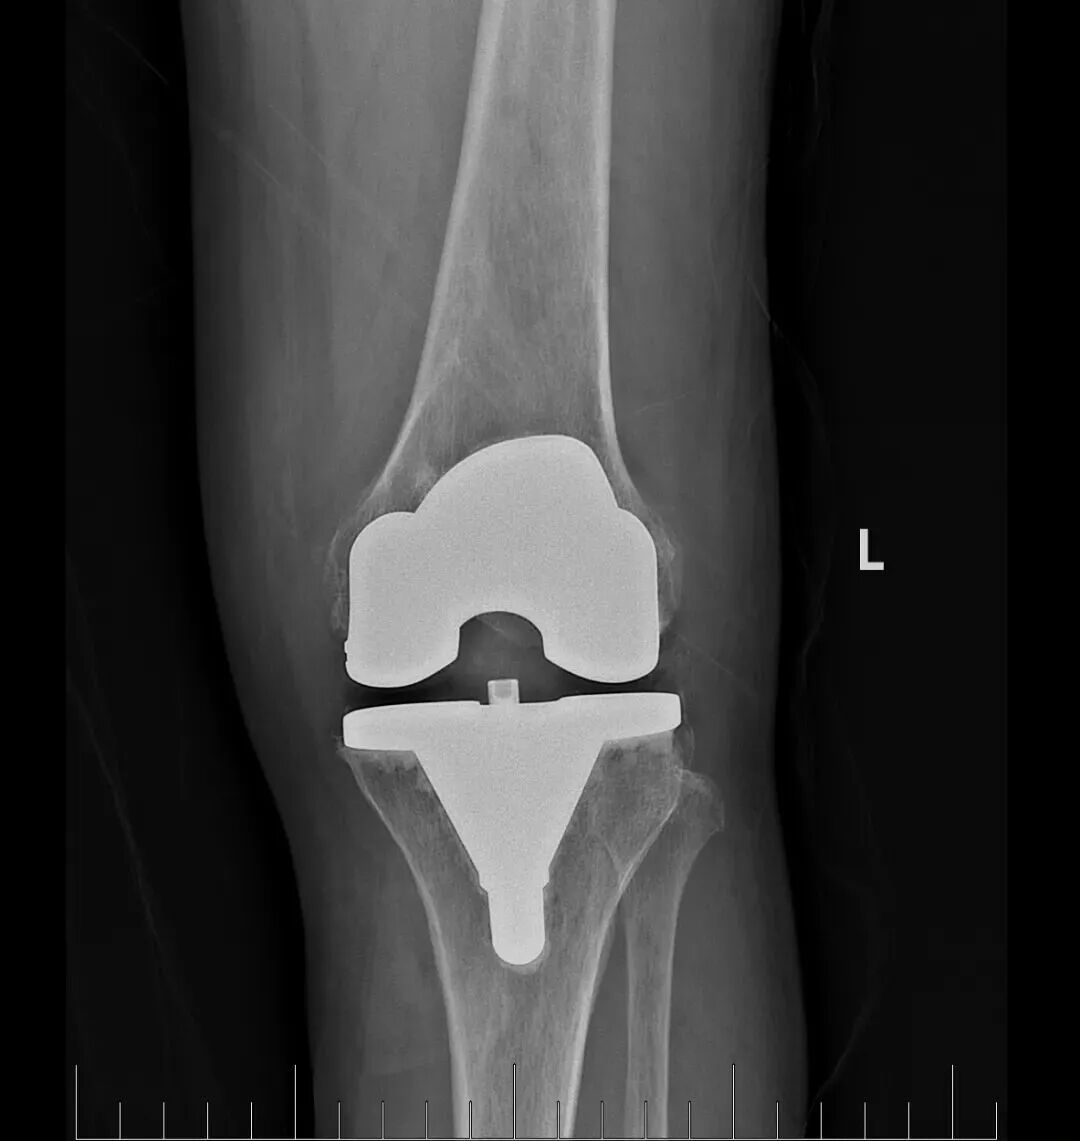

在充分的术前准备基础上,骨科蔡志荣主任带领团队,为李女士实施了左侧全膝关节置换术。团队凭借精湛的操作技术,精准完成了假体植入与软组织平衡,术中出血量仅30毫升,无需输血,患者生命体征平稳。得益于“快速康复外科”理念的应用,李女士在术后第二天就能在助行器辅助下站立并行走。恢复速度远超传统关节置换术后的康复进程,患者及家属对治疗效果赞不绝口。

此次手术的成功开展,是玉溪市中山医院骨科在复杂关节置换手术上技术的更进一步,也体现了多学科协作模式对于合并多种基础疾病患者的救治优势。蔡志荣主任表示,医院骨科团队将继续秉持精准医疗与快速康复相结合的理念,持续提升医疗技术水平,以更优质的医疗服务,为玉溪及周边地区的骨病患者祛除病痛,守护百姓骨骼健康。